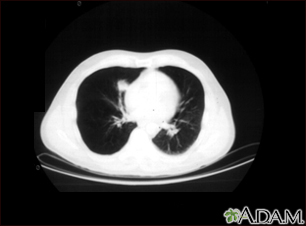

Nódulo pulmonar, pulmón inferior derecho - Tomografía computarizada

Tomografía computarizada que muestra una masa en la parte inferior derecha del tórax, cerca del corazón (lado izquierdo de la fotografía).